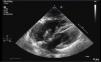

Acute coronary syndrome was suspected, so a transthoracic echocardiogram was performed, which revealed an image consistent with very long, mobile thrombi in both the left atrium and the right atrium each measuring approximately 4cm, that appeared to cross continuously through a patent foramen ovale, suggestive of thrombus in transit (Fig. 1). Findings consistent with severe pulmonary hypertension and severe right ventricular dilatation and dysfunction were also observed.

To confirm the presence of thrombus in transit, the study was completed with a transesophageal echocardiogram, and a chest CT was requested in which acute pulmonary thromboembolism (PTE) was identified with bilateral involvement from the main branches, along with data suggestive of pulmonary hypertension and right cavity overload.